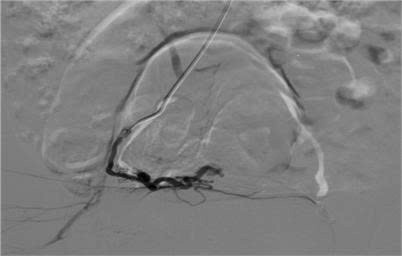

ra-mau-2.jpg

Hình ảnh kiểm tra sau nút mạch - Ảnh BVCC